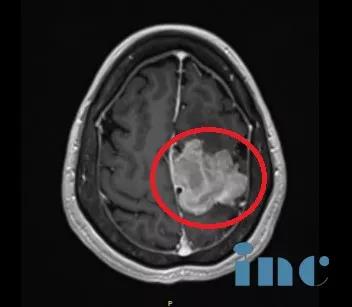

手術(shù)過程:左側(cè)額葉到額頂葉旁矢狀面的成骨性環(huán)鋸術(shù)和顯微外科腦膜瘤切除術(shù);自體骨膜移植的硬腦膜成形術(shù)。

術(shù)后影像資料:腫瘤肉眼下全切,可見局部組織缺陷,水腫效應(yīng)存在,被壓迫正常腦組織緩慢復(fù)位。